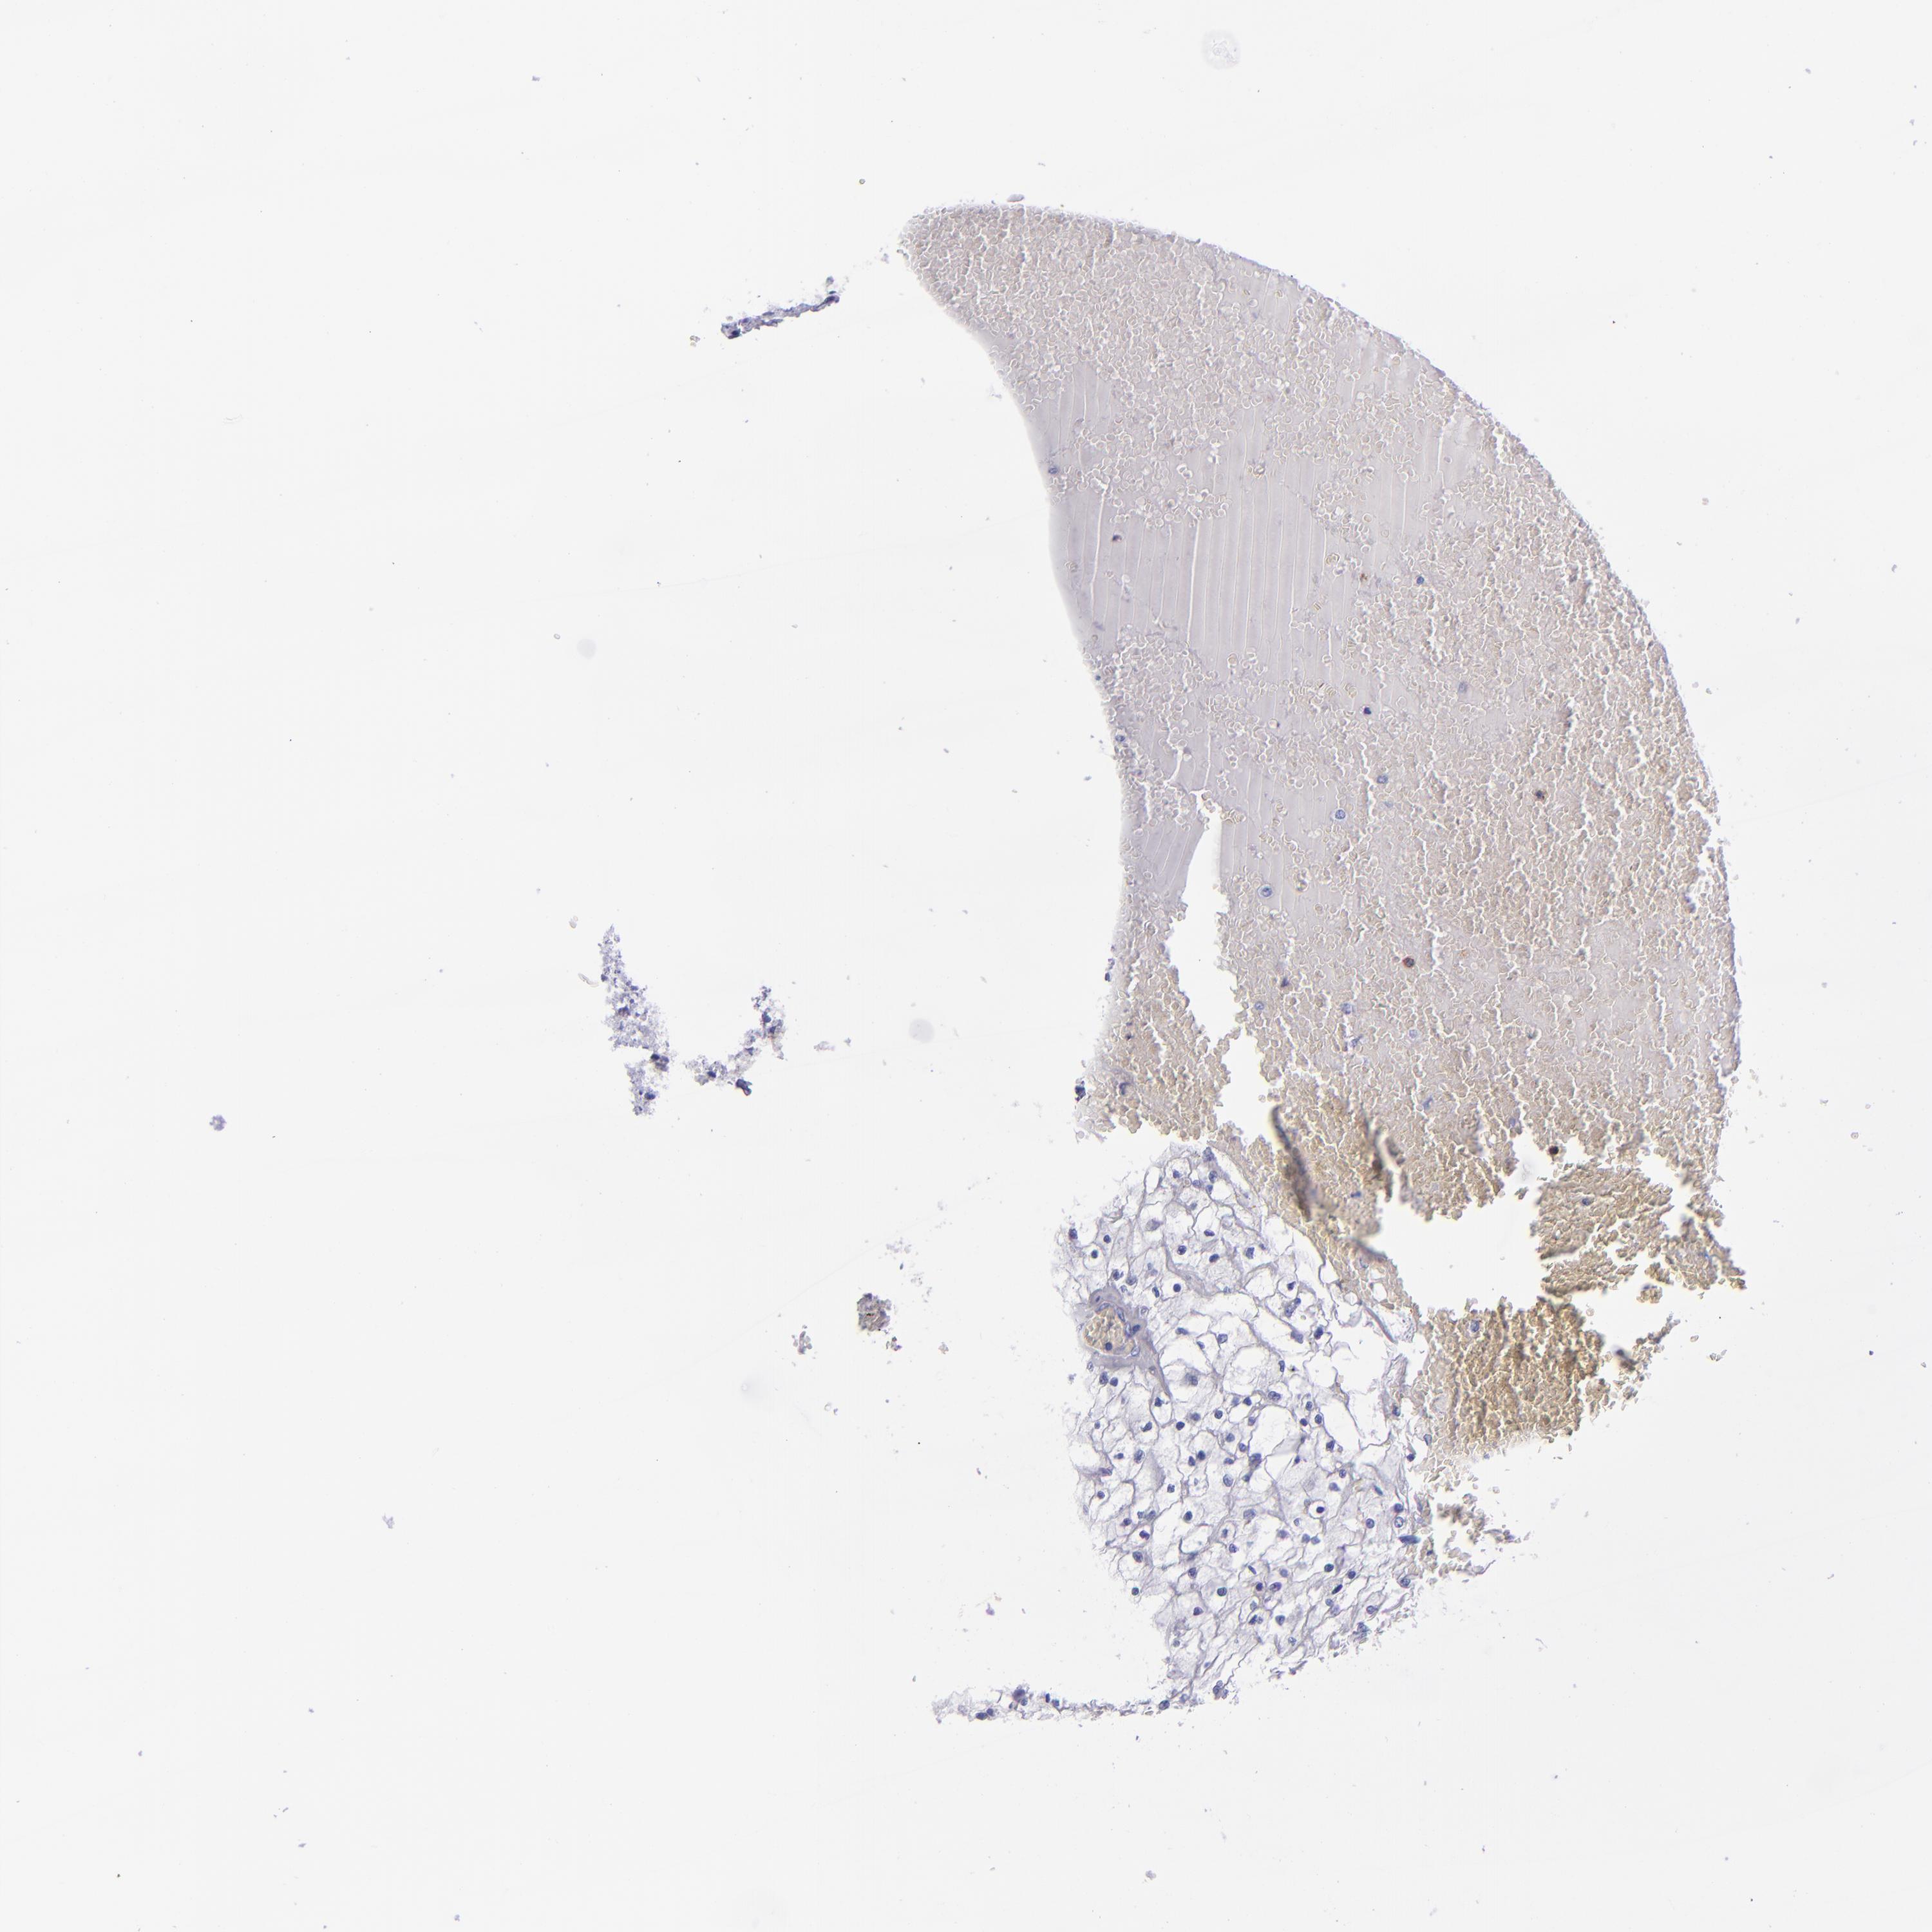

KIDNEY RENAL CLEAR CELL CARCINOMA (VALIDATION) - Interactive survival scatter ploti

The Survival Scatter plot shows the clinical status (i.e. dead or alive) for all individuals in the patient cohort, based on the same data that underlies the corresponding Kaplan-Meier plots. Patients that are alive at last time for follow-up are shown in blue and patients who have died during the study are shown in red.

The x-axis shows the expression levels (FPKM) of the investigated gene in the tumor tissue at the time of diagnosis. The y-axis shows the follow-up time after diagnosis (years). Both axes are complimented with kernel density curves demonstrating the data density over the axes. The top density plot shows the expression levels (FPKM) distribution among dead (red) and alive patients (blue). The right density plot shows the data density of the survived years of dead patients with high and low expression levels respectively, stratified using the cutoff indicated by the vertical dashed line through the Survival Scatter plot. This cutoff is automatically defined based on the FPKM cutoff that minimizes the p-score. The cutoff can be changed by dragging the vertical line or by entering a cutoff value in the square labeled "Current cut-off".

Under the Survival Scatter plot the p-score landscape (black curve; left axis) is shown together with dead median separation (red curve; right axis). Dead median separation is the difference in median mRNA expression between patients who have died with high and low expression, respectively. It is calculated as follows: median FPKM expression of dead patients with high expression - median FPKM expression of dead patients with low expression. This is intended to aid the user in visually exploring custom cutoffs and the associated p-scores and dead median separation.

Individual patient data is displayed and can be filtered by clicking on one or more of the category buttons on the top of the page. Categories describing expression level and patient information include: high, low, alive, dead, female, male and tumor stages. The scale of the x-axis can be toggled between linear and log-scale by clicking on the "x log" button. Mouse-over function shows TCGA ID, patient information and mRNA expression (FPKM) for each patient.

& Survival analysisi

Kaplan-Meier plots summarize results from analysis of correlation between mRNA expression level and patient survival. Patients were divided based on level of expression into one of the two groups "low" (under cut off) or "high" (over cut off). X-axis shows time for survival (years) and y-axis shows the probability of survival, where 1.0 corresponds to 100 percent.

CR1 is not prognostic in Kidney Renal Clear Cell Carcinoma (validation)

: 1.13

Average pTPM 2.0

Number of samples 100